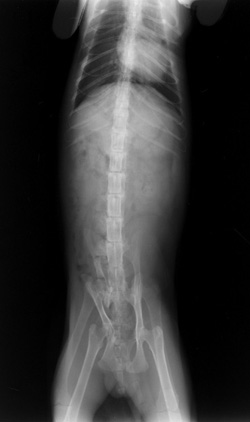

Double Exposures